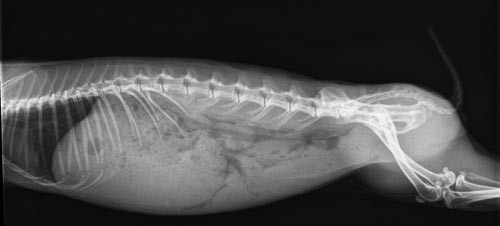

Weterynarz obmaca chory brzuch, dla potwierdzenia diagnozy powinno być wykonane RTG.

Na zdjęciu widać powiększony żołądek, wypełniony treścią pokarmowa.

Królik miniaturka

Źródło zdjęcia: http://www.kaninchenberatung.de

Wzdęcie byłoby widoczne jako czarne pole wypełniające żołądek, także zator kula włosowa można

odróżnić od przepełnienia.